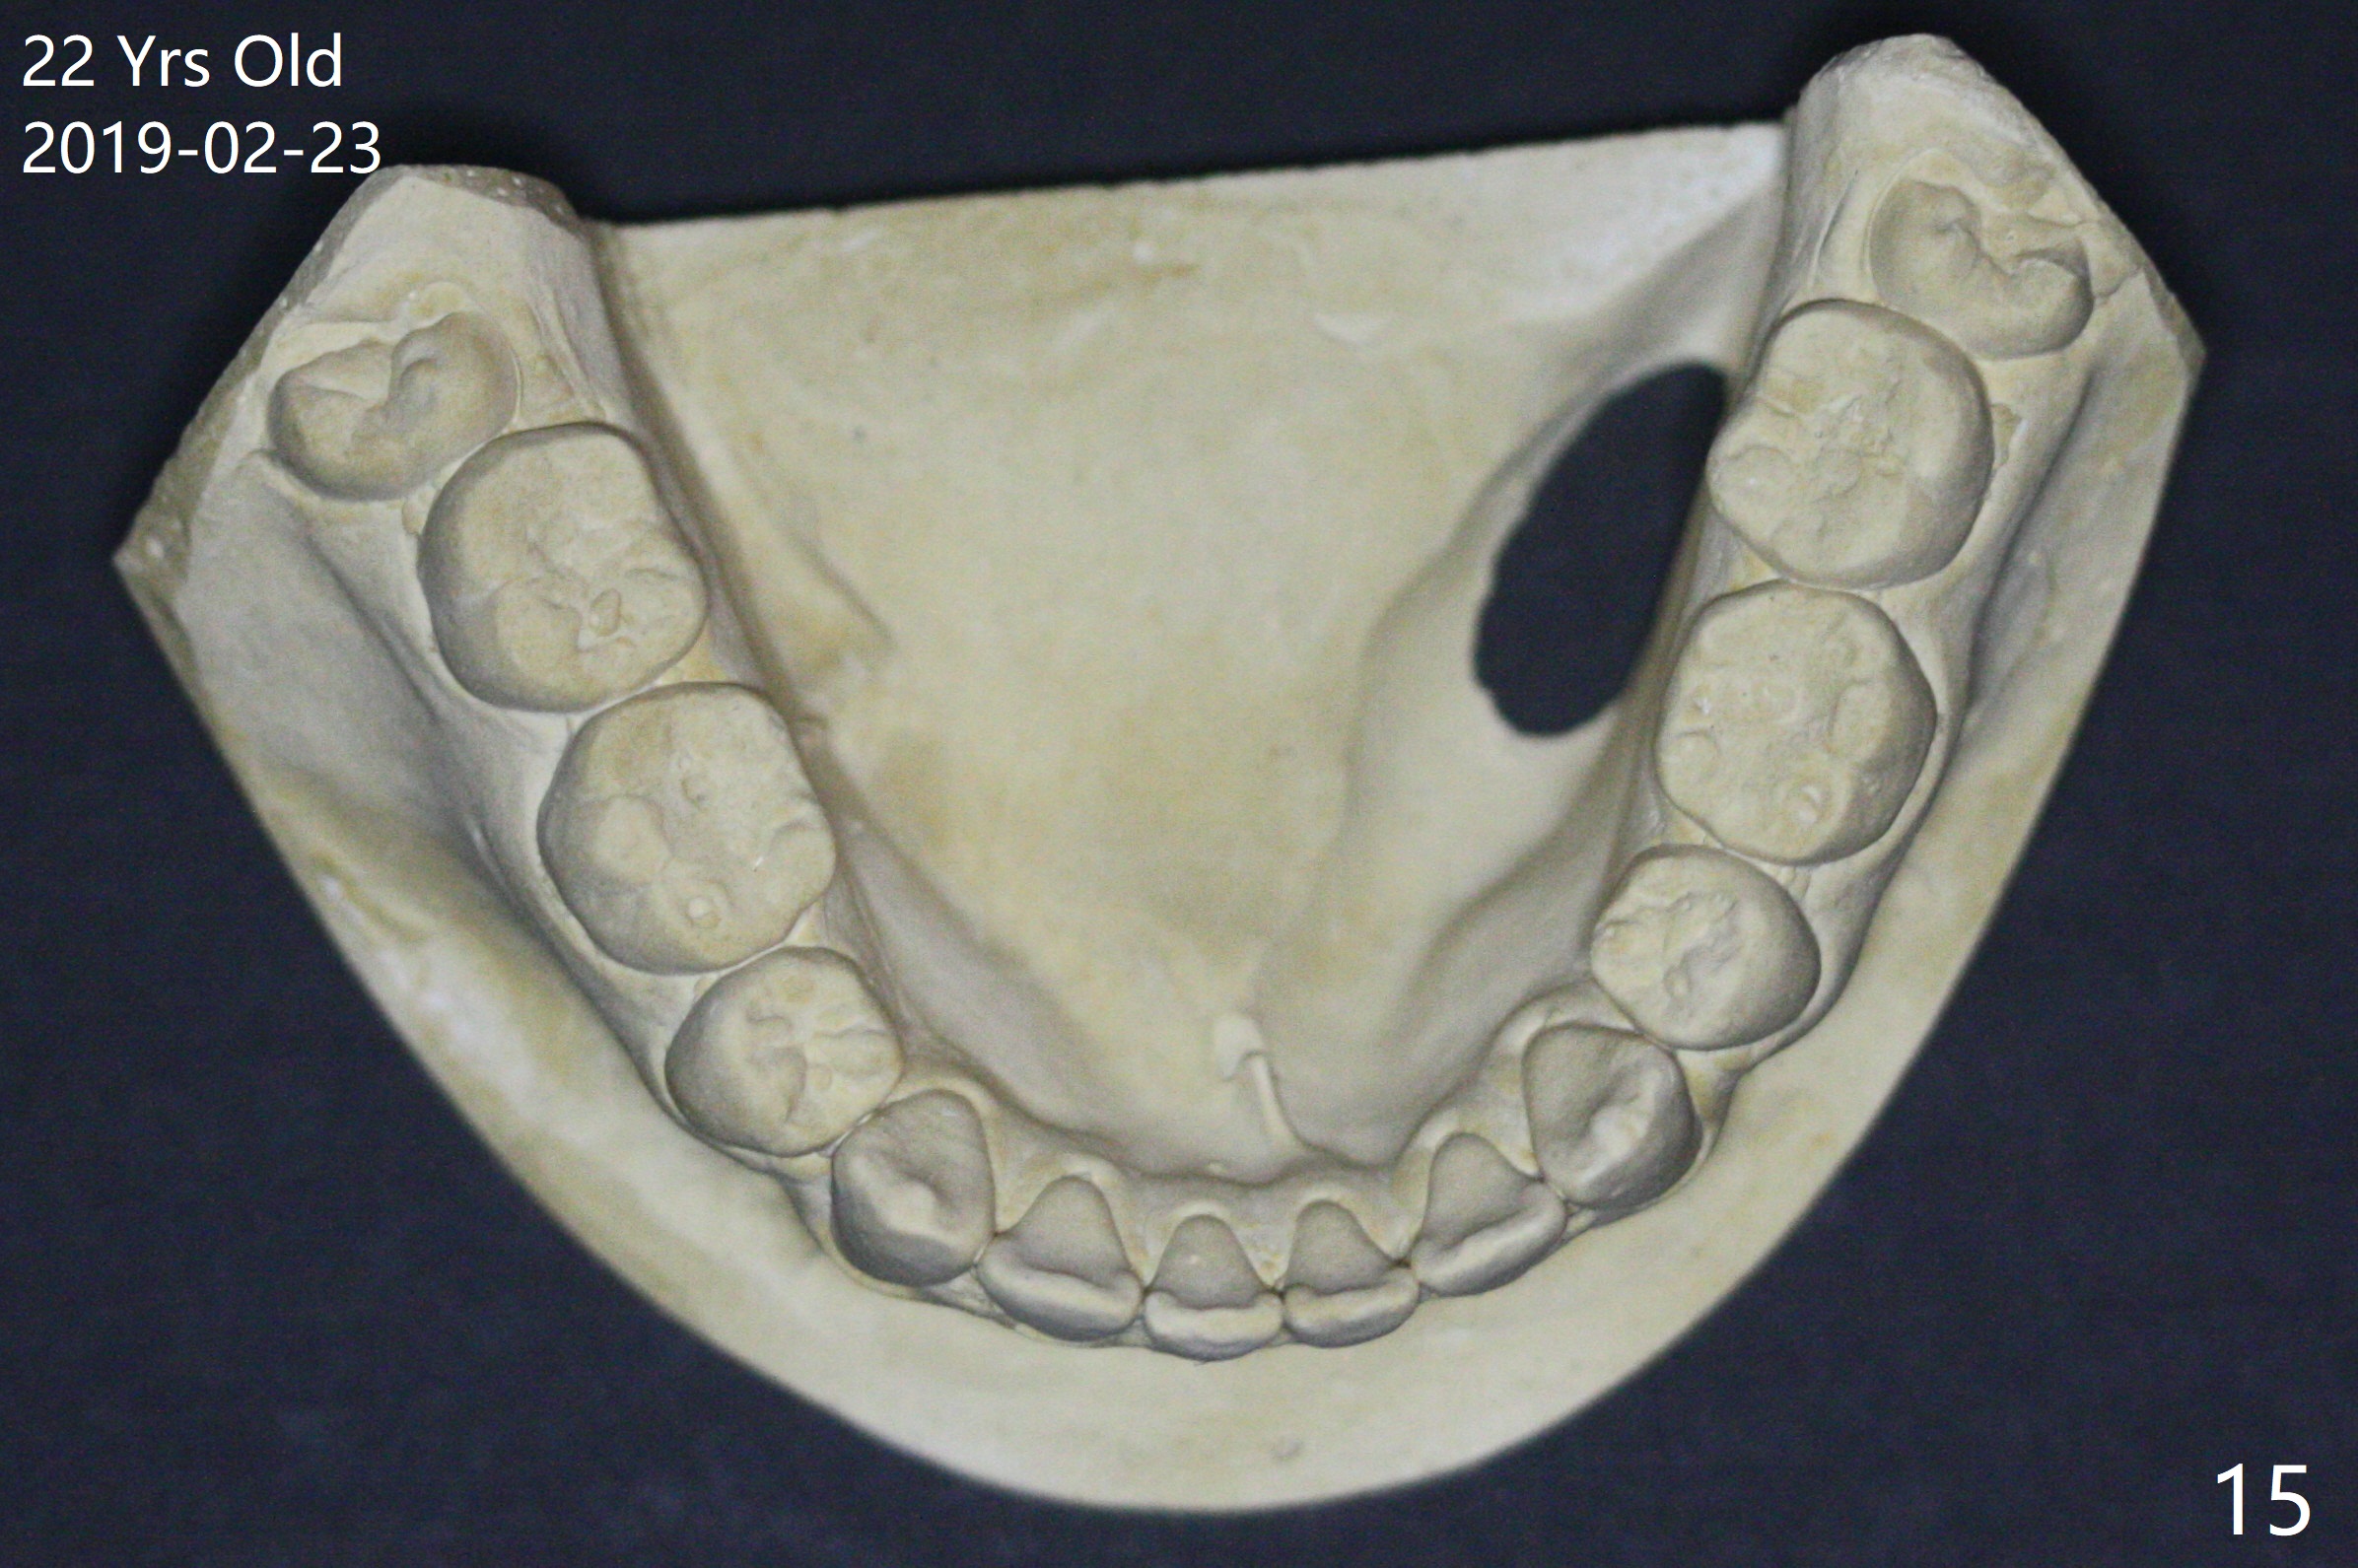

A 16-year-old man has severe crowding, but the open bite is ignored (Fig.1,4,7,10,13). The orthodontic treatment lasts 4 years 5 months, including failure to return for a period of time. The open bite seems to have been corrected (Fig.2, 5, 8, 11, 14). Suction down retainers are provided. In less than 2 years, the patient returns requesting remaking retainers. It appears that open bite relapses (Fig.3,6,9,12,15), as related to supraeruption of the lower 2nd molars (Fig.6,9 arrows). The latter is apparently associated with the erupting 3rd molars.